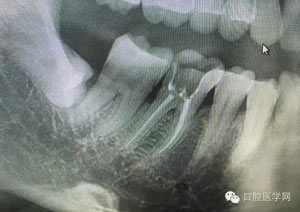

病例1:患者迫切希望保留自己的這一顆牙齒,根尖周陰影比較大,二度松動.而且旁邊有種植修復(fù)體,和患者溝通好后,治療好后觀察一個月后冠修復(fù),因為有種植的后期修復(fù),所以有了機會觀察,術(shù)后三個月和術(shù)后四個月,根尖恢復(fù)的還算不錯,希望能夠繼續(xù)觀察下去.這樣子的病例,做的時候我們一定要非常的小心,和患者要有充分的溝通以及不同科室的溝通然后決定怎么樣做比較好,假如就是出現(xiàn)了問題,到時候我們也比較好處理些,免得我們自己到時候不好收場。